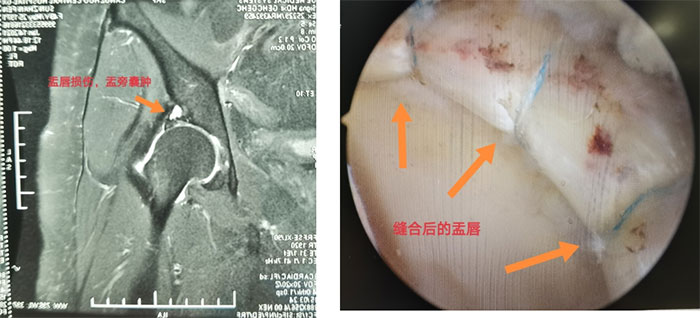

其中,肩關(guān)節(jié)鏡下上關(guān)節(jié)囊重建治療巨大不可修復(fù)性肩袖損傷已累計(jì)數(shù)十例,填補(bǔ)河北省技術(shù)空白,達(dá)到國內(nèi)先進(jìn)水平。髖關(guān)節(jié)鏡下盂唇損傷的縫合修復(fù);肘關(guān)節(jié)鏡下關(guān)節(jié)僵硬清理松解,踝關(guān)節(jié)鏡下韌帶損傷的修復(fù)均達(dá)到國內(nèi)先進(jìn)水平??剖业倪\(yùn)動康復(fù)專業(yè),讓患者術(shù)后即刻獲得最精準(zhǔn)的康復(fù)治療。康復(fù)與臨床治療密切結(jié)合,許多專業(yè)運(yùn)動員經(jīng)運(yùn)動醫(yī)學(xué)科治療,恢復(fù)到了損傷前的運(yùn)動水平??剖覉?jiān)持走專業(yè)化發(fā)展道路,極大地推動了滄州地區(qū)運(yùn)動醫(yī)學(xué)事業(yè)的發(fā)展。

髖關(guān)節(jié)盂唇修復(fù)術(shù)前VS術(shù)后